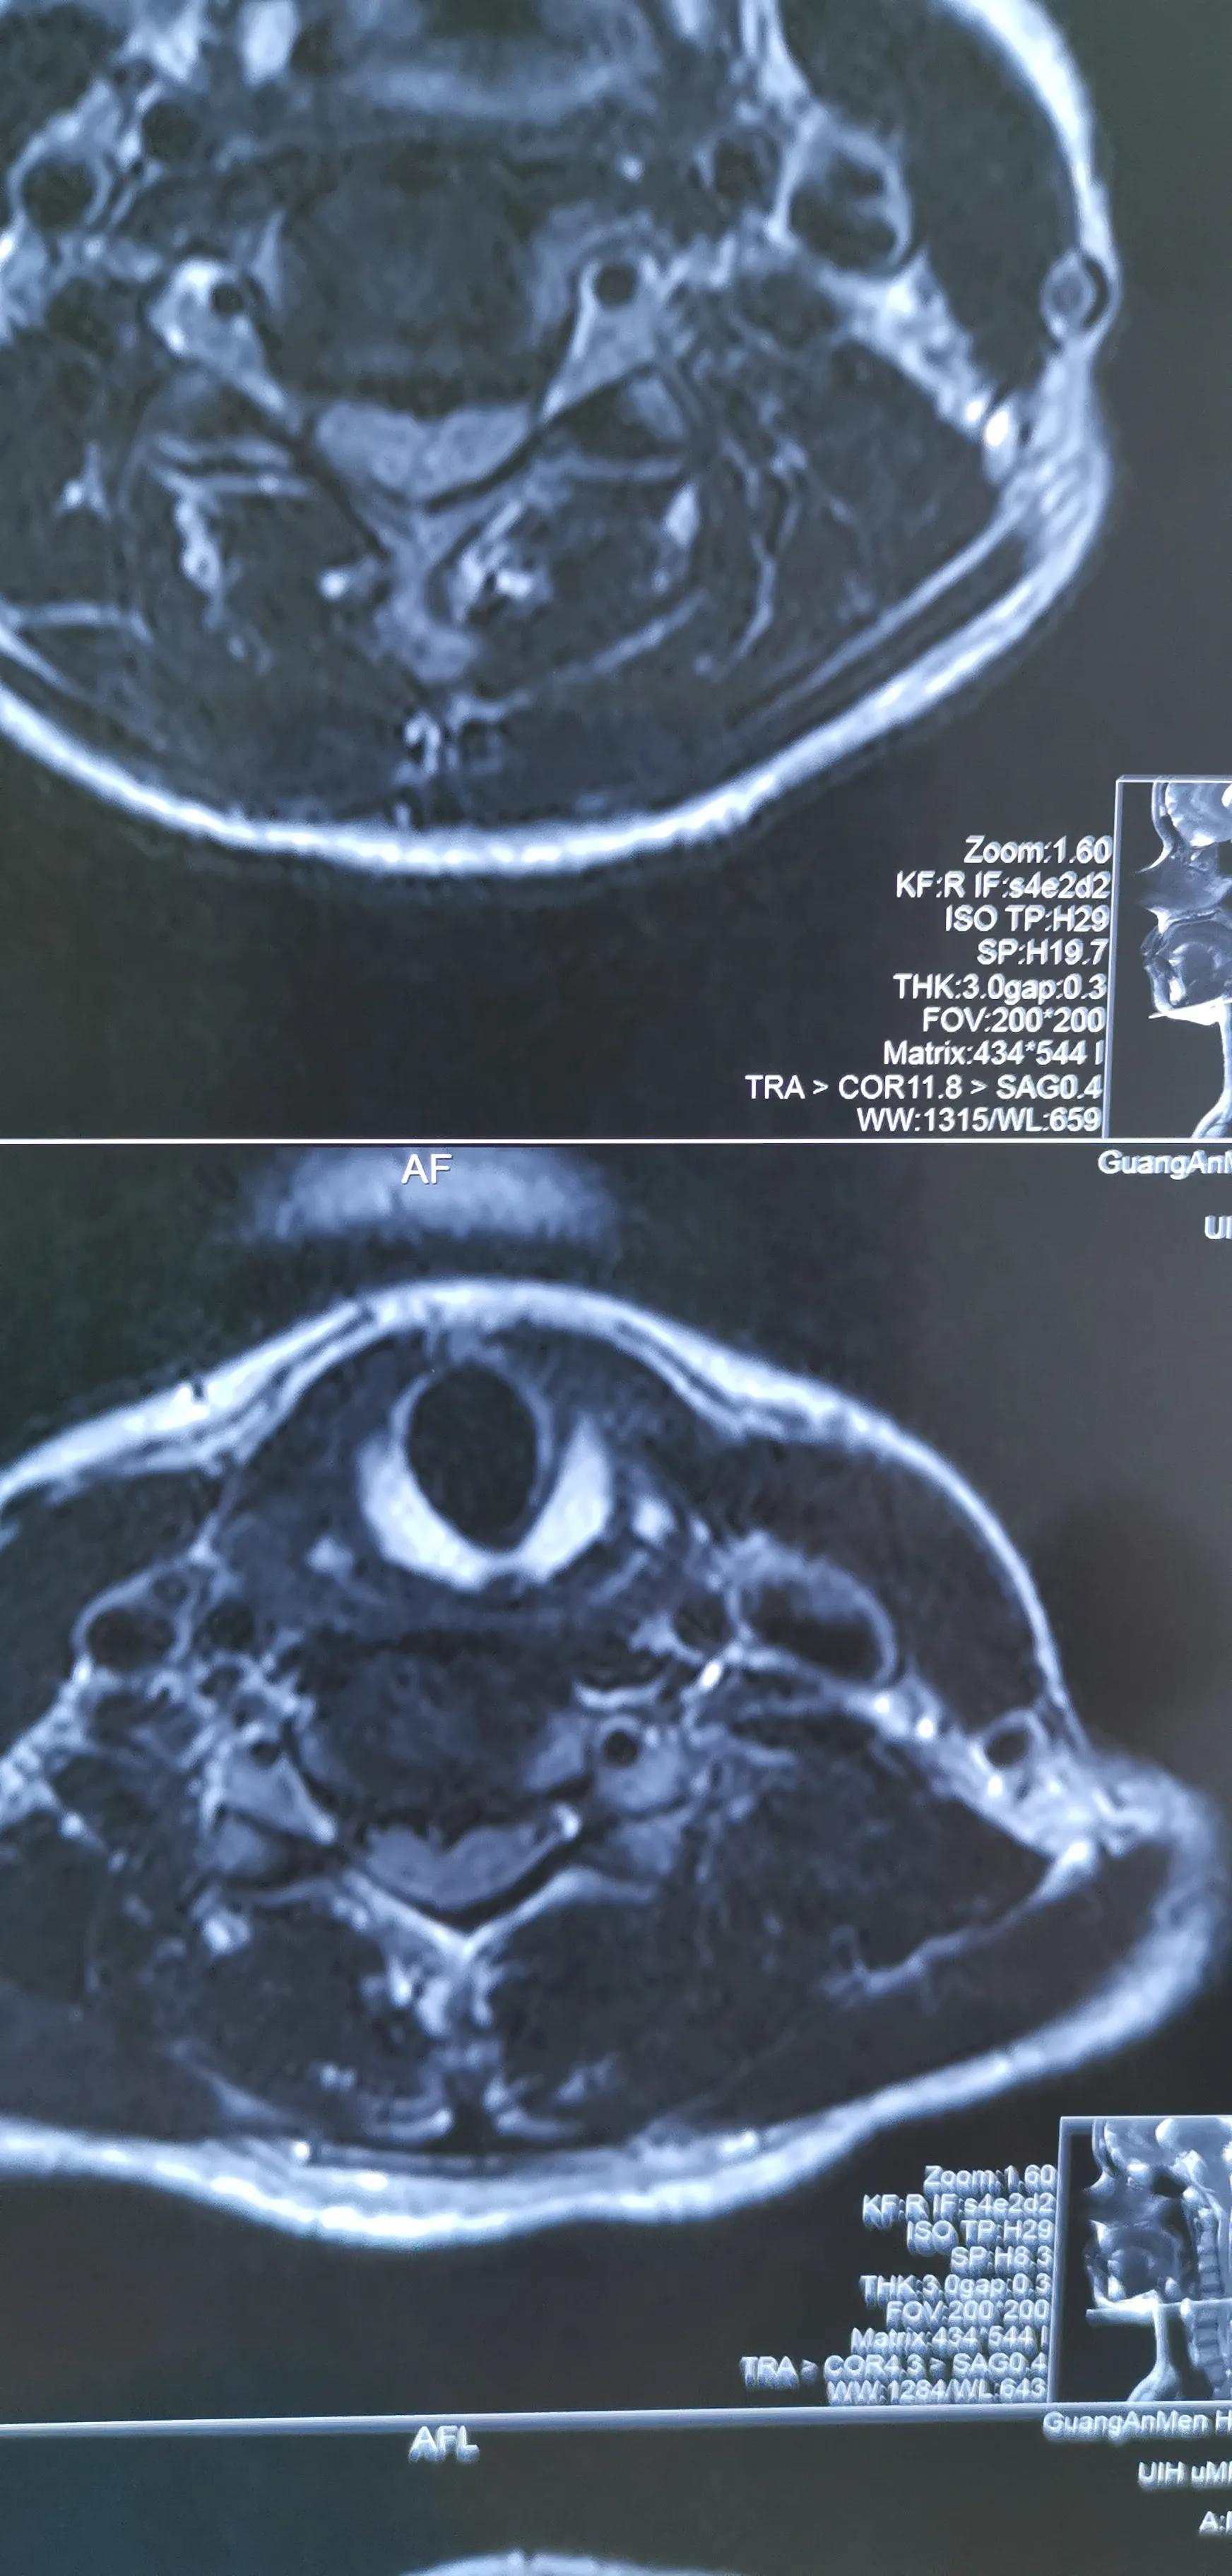

43岁女性,颈肩部疼痛严重伴左侧上肢放射痛无力,mri提示C4/5,C5/6椎间盘突出,CT提示钙化。予前路C5椎体次全切除,椎间盘摘除,椎间钛笼植骨融合钢板内固定,术后疼痛基本消失,肌力逐渐恢复,麻木缓解。

对这类椎间盘突出钙化的患者如果疼痛严重或伴肌力下降或行走不稳,提示压迫神经或脊髓,不宜推拿,可手术减压,效果显著。